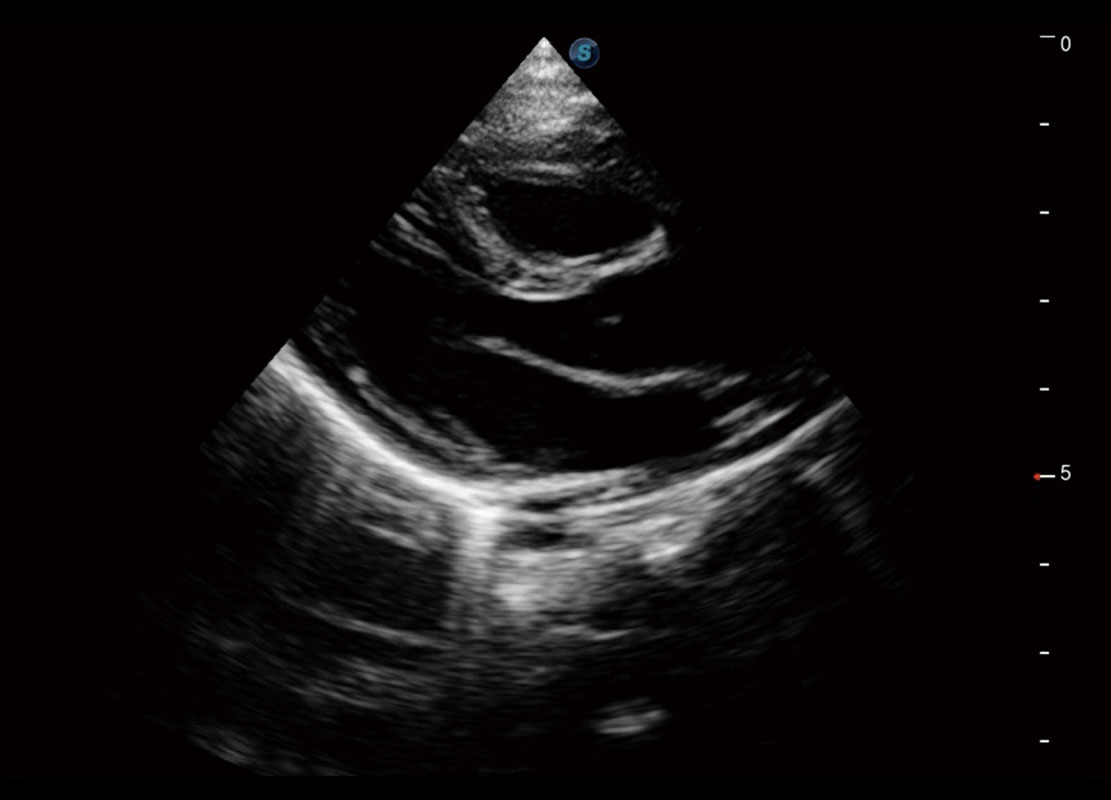

P60搭载一系列胎儿心脏成像技术,实现精细的胎儿心脏评估。

四腔切面

右室双出口